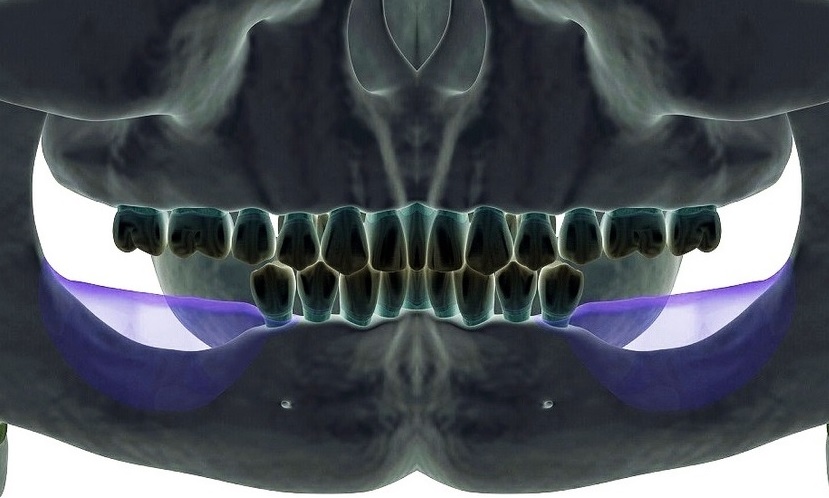

Diş kemik erimesi, dişleri destekleyen ve çevreleyen kemik dokusunun kaybı anlamına gelir. Çene kemiğinin yapısında meydana gelen bozulmaları ifade eder.

Bu durum, dişlerin kaybolmasına ve çene kemiğinin yapısının değişmesine yol açabilir. Dolayısıyla erken teşhis ve tedavi bu sürecin yönetilmesinde kritik öneme sahiptir.

3. İmplant Uygulamaları

- Dental İmplantlar: Kaybedilen dişlerin yerine çene kemiğine yerleştirilen yapay köklerdir.

- All-On-Four İmplant: Dört implant üzerine tam bir diş setinin monte edildiği bir tekniktir.

- Zygoma İmplant: Üst çene kemiği yeterli olmayan hastalarda kullanılan, zigomatik kemiğe yerleştirilen uzun dental implantlardır.